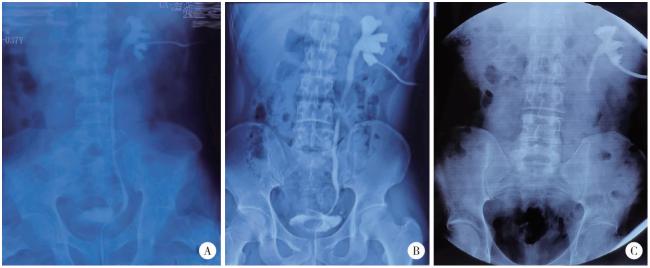

中位随访时间为14.2(6.1~107.1)个月,总体成功率97.2%(图 2)。手术前后肌酐分别为(91.29±23.46) μmol/L vs.(92.15±23.10) μmol/L(P=0.572),估算肾小球过滤率分别为(83.81±20.21) mL/(min·1.73 m2) vs.(81.35± 18.59) mL/(min·1.73 m2)(P=0.204)。1例患者在球囊扩张术后1年出现肾积水加重,影像学检查提示输尿管狭窄,再次手术应用阑尾补片重建输尿管,术后随访1年,肾积水程度减轻。1例回肠代输尿管患者术后14个月积水程度加重,保守观察,继续随访4年肾积水稳定。术后并发症见表 3

图2 结石相关输尿管狭窄的不同重建手术策略

Figure 2 Different surgical strategies for stone related ureteral stricture

A, ureteroureterostomy; B, ureteral reimplantation (psoas hitch); C, autologous mucosal graft ureteroplasty; D, ileal ureter replacement.